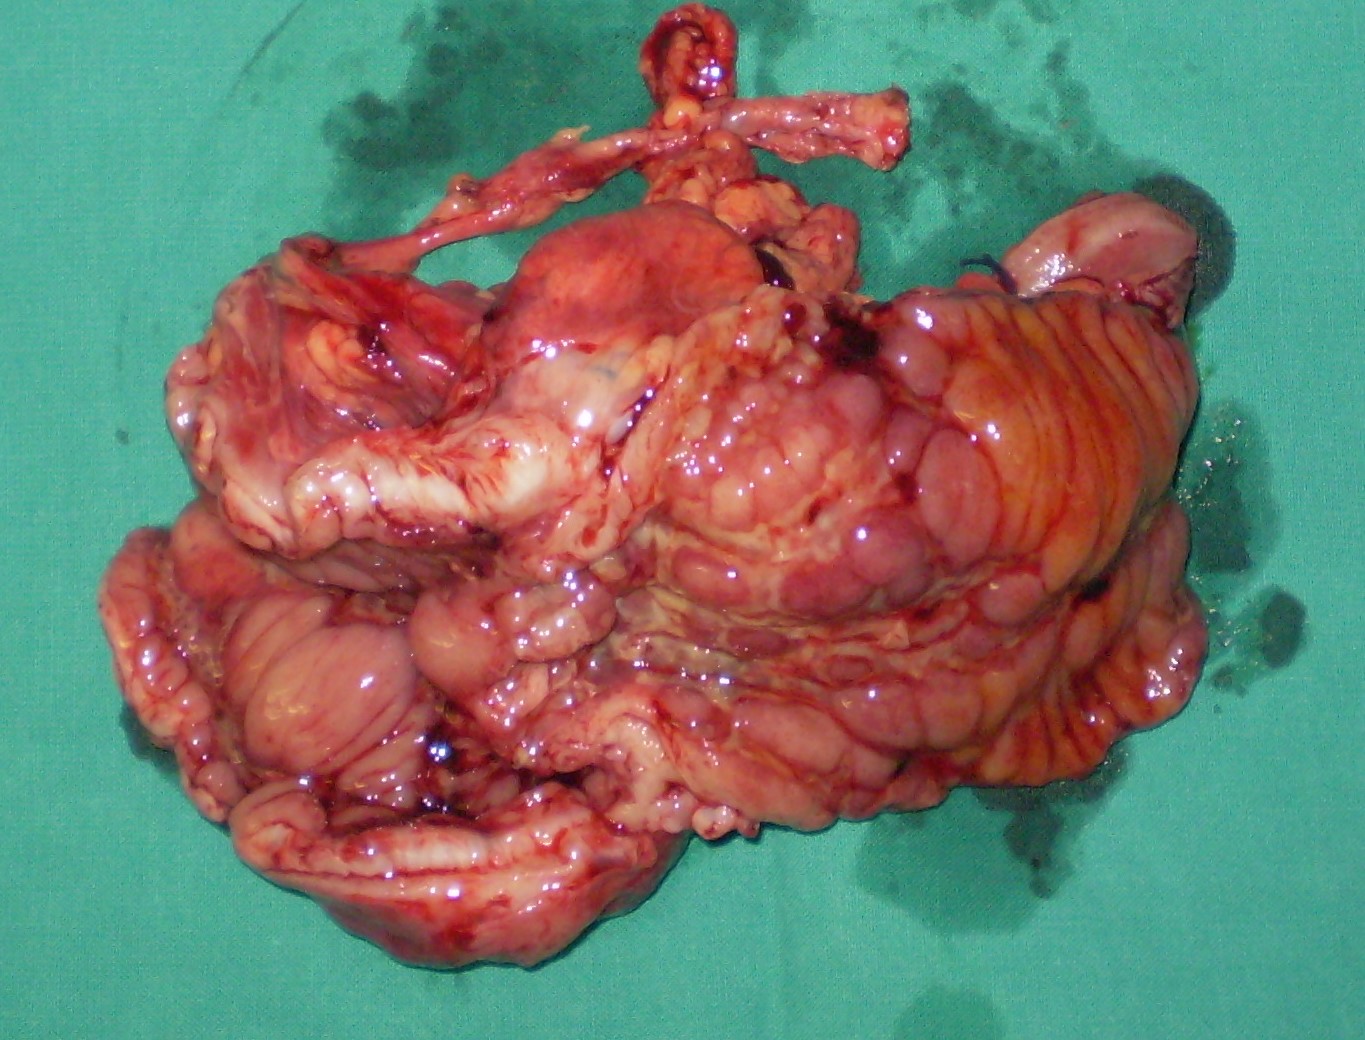

Παρασκεύασμα δεξιάς ημικολεκτομής. Το ενσφηνωμένο βλεννοκοπρανώδες υλικό στον τελικό ειλεό είναι εμφανώς ορατό (Ευγενική παραχώρηση Dr. V. Penopoulos)